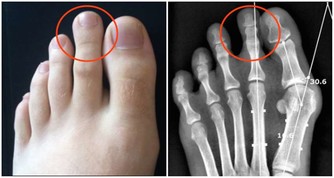

腎積水是一種慢性腎髒病,腎積水的成因是由於腎結石堵塞導致尿液聚積在腎臟內,不能及時排出。如果結石不能及時排出,長時間腎積水,久而久之就會影響到腎臟的功能。